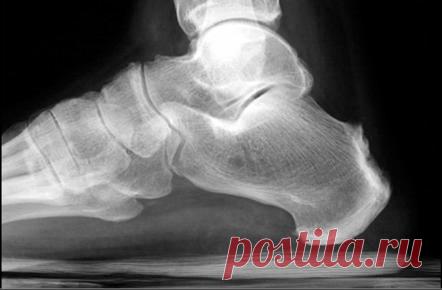

Гетерогенная группа воспалительных ревматических заболеваний с преимущественным вовлечением осевых и периферических суставов и энтезитов (воспаление на месте соединения сухожилий и связок к кости). Они также имеют другие функции, такие как передний увеит и поражения кишечника, сходного с болезнью Крона. Симптомы в пределах определенных причин могут пересекаться и могут переходить от одного к другому. Существует высокая частота встречаемости НLA-B27, но отрицательные анализы на ревматоидный факто